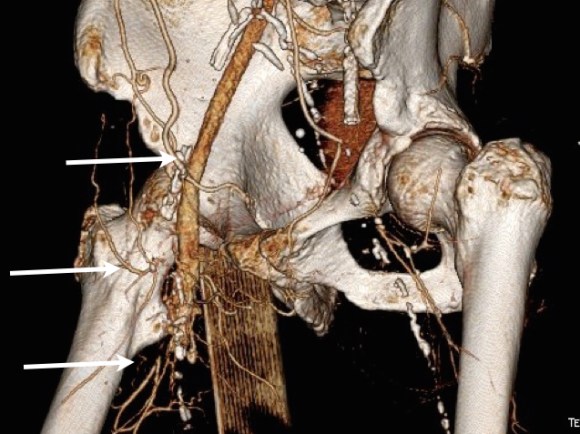

The other interesting finding was that he had an abundance of very good vein. Following surgical dictum, his original and subsequent surgeons had used his vein from his contralateral saphenous vein. His right leg, fused at the knee, lacked a good calf muscle pump action. While there were no varicose veins, the greater and lesser saphenous veins were large and generous conduits, at least by 3DVR imagery, confirmed on duplex (image below, white arrows).